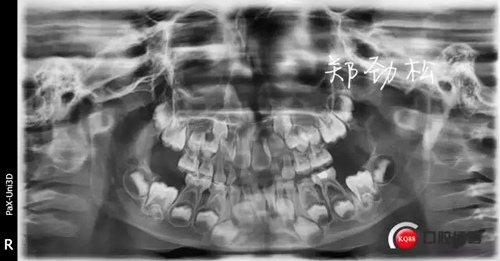

病例一

主訴:牙齒反復(fù)發(fā)炎近一年

現(xiàn)病史:患兒父親代述一年前患兒前牙在外院做過(guò)根管治療,后前牙唇側(cè)牙齦反復(fù)膿腫前來(lái)就診。

檢查:7A牙體變色,舌側(cè)有充填物,叩診(++),松一度,冷熱刺激無(wú)反應(yīng),唇側(cè)牙齦紅腫有一瘺管。

診斷:7A慢性根尖炎

處置:開(kāi)隨,去除根充物后沖洗引流。

此病例術(shù)后取出根充物發(fā)現(xiàn)其中有兩根牙膠尖,其實(shí)大家都知道乳牙的牙根隨著恒牙的萌出會(huì)逐漸吸收,而牙膠尖不能被吸收,所以牙膠尖不能夠用作乳牙根充,我常規(guī)選擇vitapex糊劑作為乳牙的根充材料。